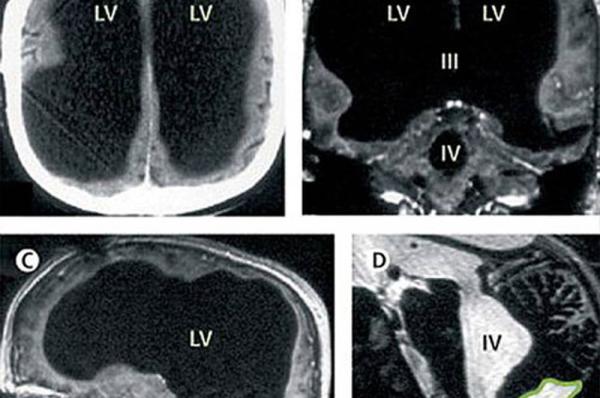

X光片显示,该男子75%的脑组织已消失不见。

据英国媒体报道,法国一名男子曾因腿部疼痛去医院检查,医生却找不出病根。在对其进行了全身体检后才发现,原来这名男子的腿疼是由脑部病变引起的,而该男子的大脑只剩下正常人大脑体积的一半都不到了。

报道称,这件事其实发生在2007年,近日由著名医学杂志《柳叶刀》披露。这名大脑神秘消失的男子当年44岁,医生在对其进行脑部检查后发现,他左右半脑上的额叶、顶叶、颞叶及枕叶都萎缩了。

医生指出,萎缩的这些部分是控制人类运动、感觉、语言、视觉、听觉、情感及认知能力的部分。

在对这名男子的病史进行详细调查后发现,原来他童年时患有后天脑积水症。但在他14岁时,经历了分流术,随后的30年,这名男子和家人都以为完全康复了。但其实他的大脑还是在病变,最终,脑内的积水损坏了脑组织,导致其大脑50%至75%的部分都消失了。